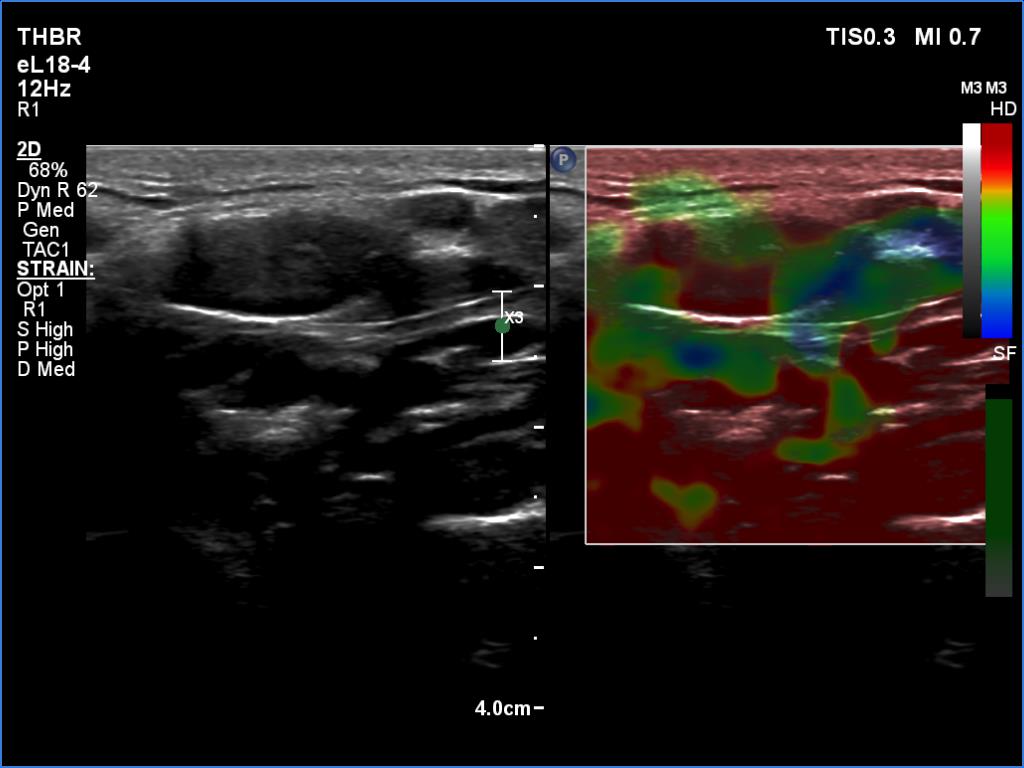

Right lobe, longitudinal scan

Left submandibular region, transverse scan, elastography. The pattern is not specific.